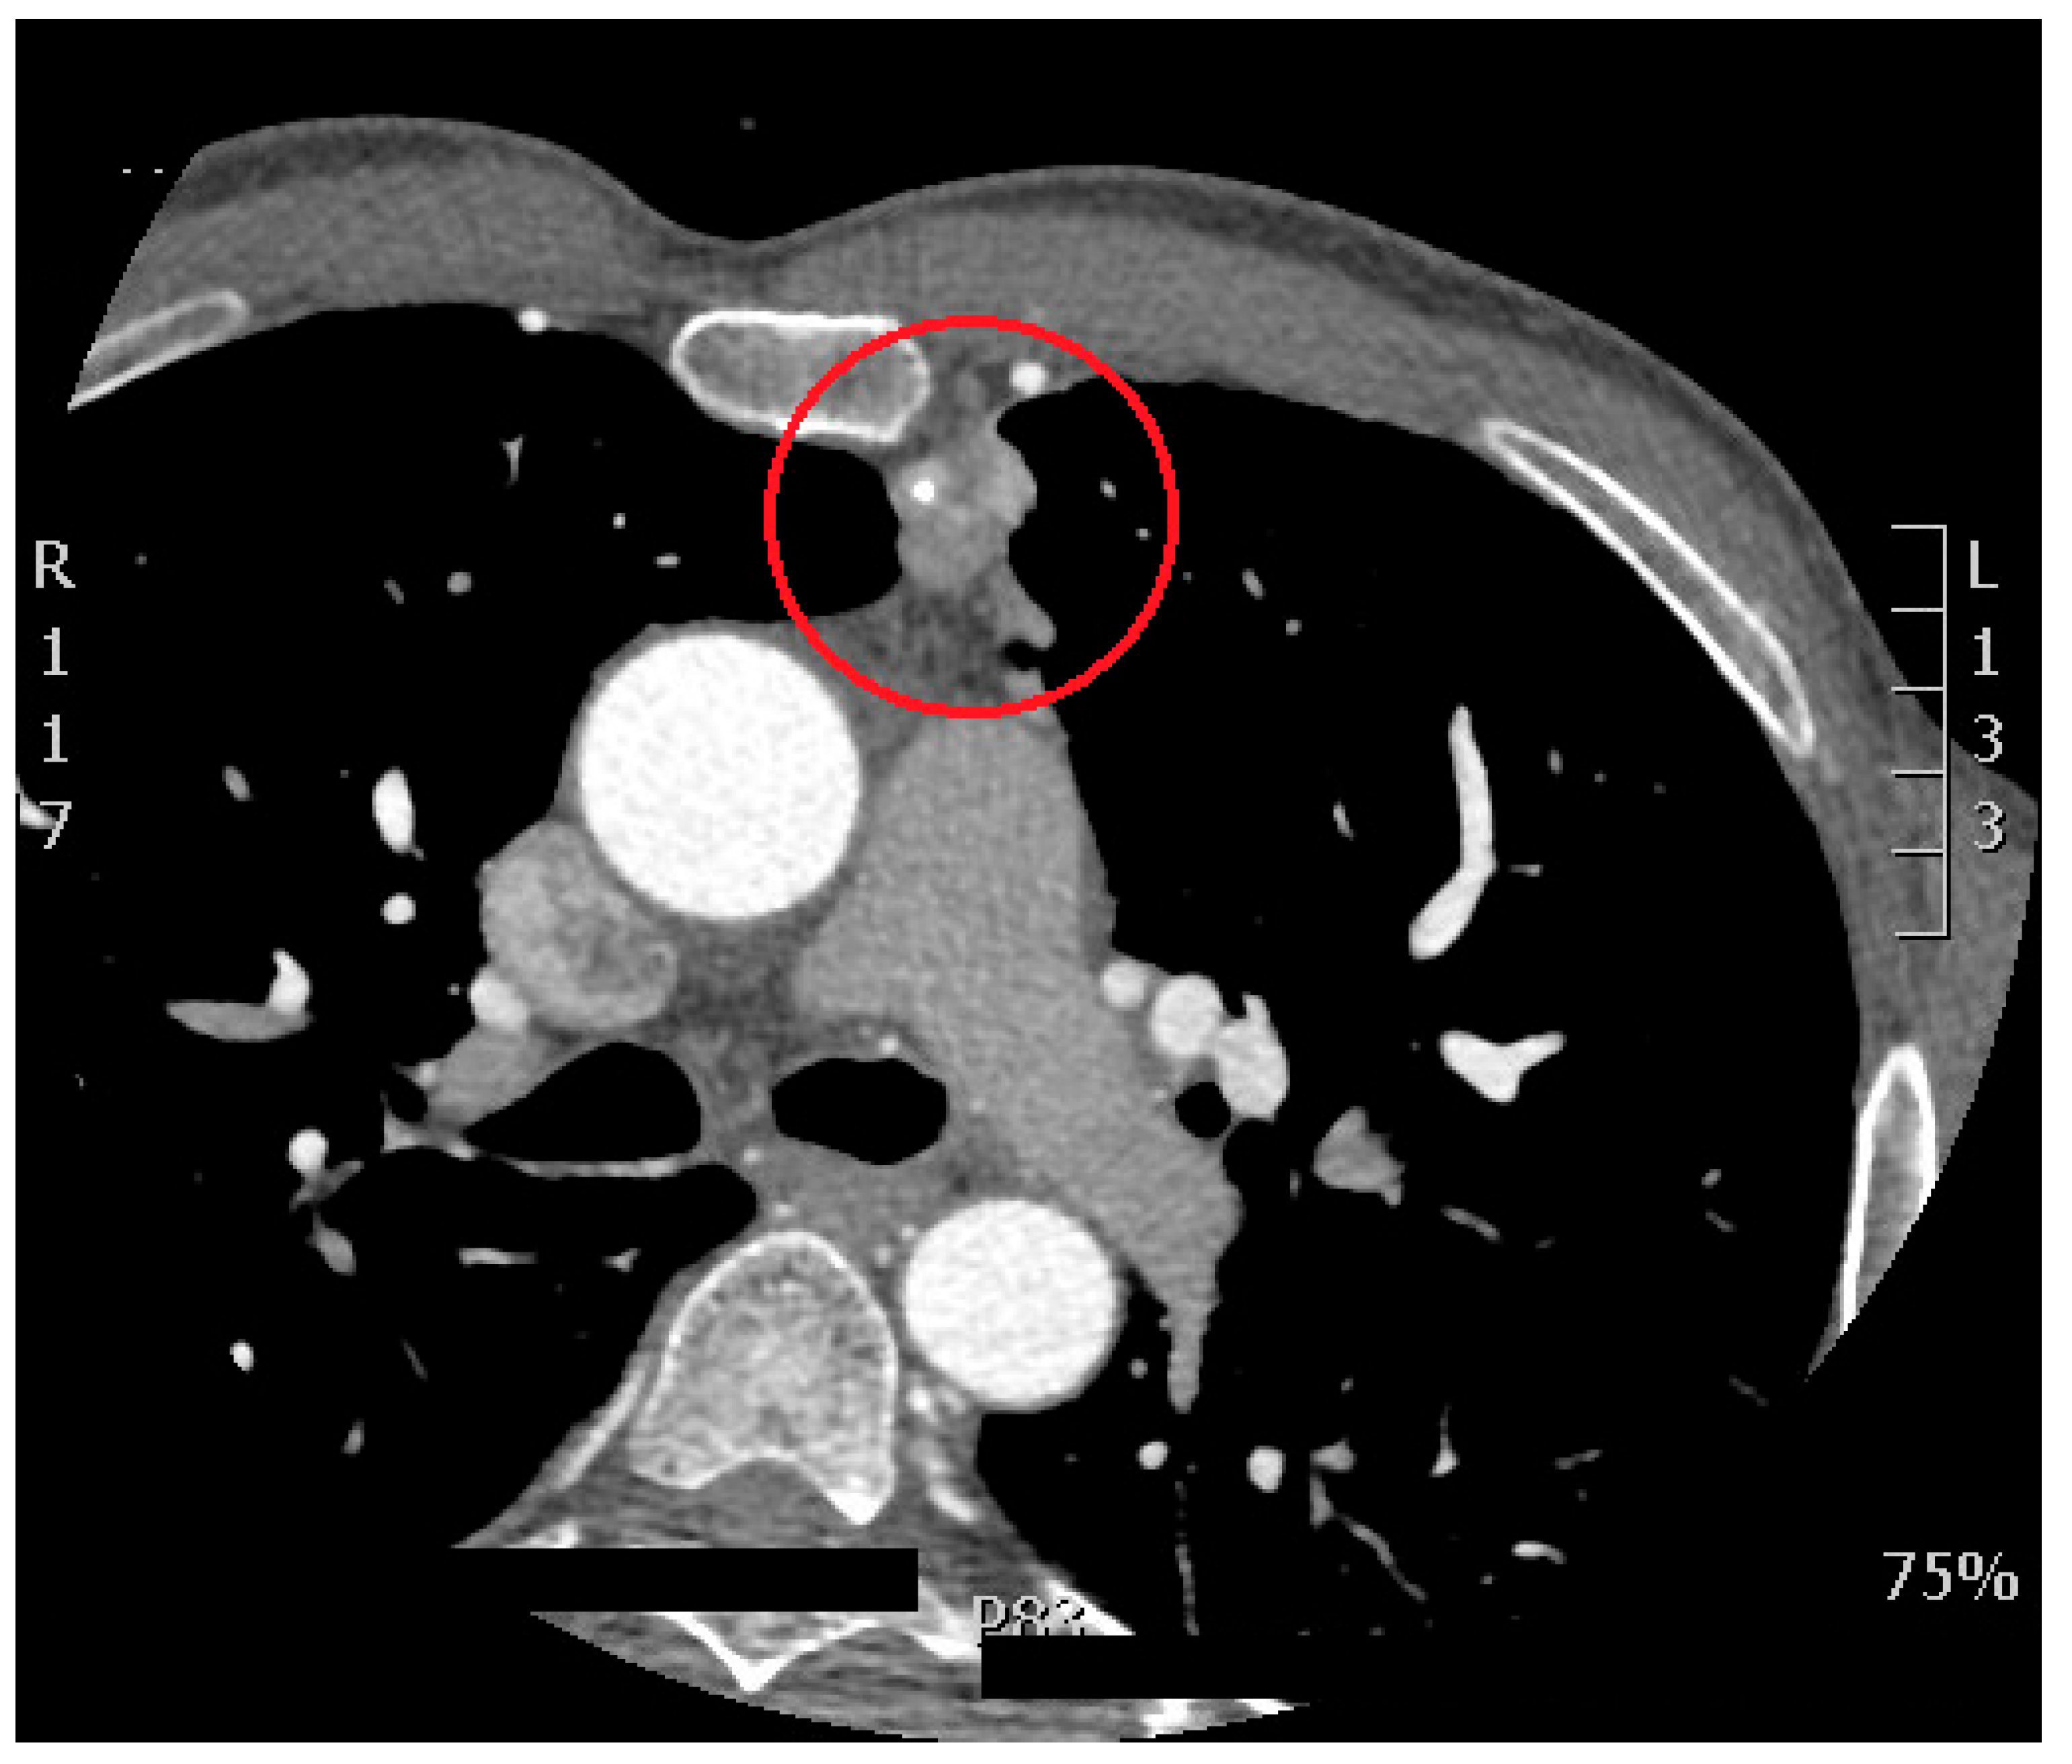

- A retrosternal mass: which was detected as a rare incidental finding during a cardiac CT scan can be clinically significant, as it may indicate a variety of underlying conditions such as malignancies, lymphadenopathy, or benign lesions like thymomas. Although it is an uncommon finding, its detection requires further investigation, as it could be associated with potentially life-threatening conditions, including lung or esophageal tumors. Early identification allows for timely intervention and better clinical management (Figure 4).